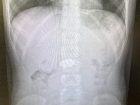

В Волгограде хирурги извлекли из желудка ребенка 5 рублей 03.03.2026 Здоровье